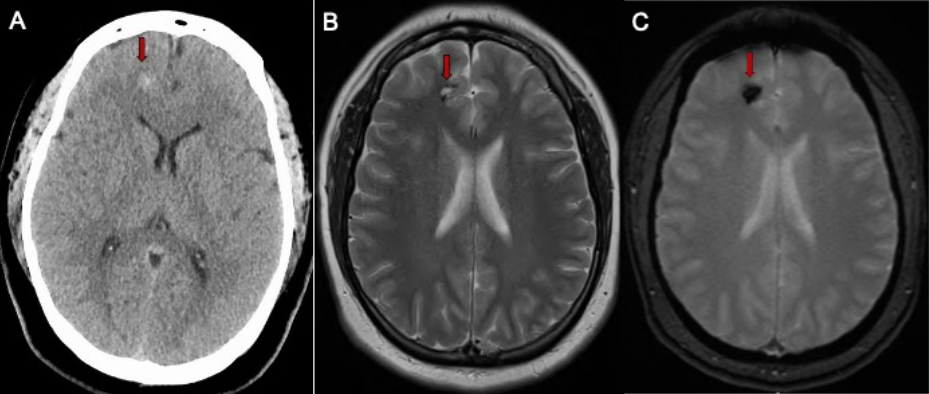

The most effective method to detect cavernous malformations is through magnetic resonance imaging (MRI) scans but other imaging studies may be needed to evaluate other characteristics of the brain and its blood vessels.

Computed Tomography Scan (CT): A CT scan is a computer reconstruction of a set of x-rays that doctors occasionally use to particularly determine whether a cavernous malformation has recently bled.

Magnetic Resonance Imaging (MRI): An MRI scan uses magnetic waves to produce a more detailed image of the brain, can identify even very small cavernous malformations, and provides details regarding the location of the lesion within the brain. MRIs are often repeated and used to monitor cavernous malformations for growth.

Figure 2: A. CT scan of the brain in a patient with a mild headache showing a small spot of white bleeding (red arrow). B. Brain MRI scan showing a small cavernous malformation (red arrow) in the frontal lobe. C. GRE Brain MRI sequence confirms the presence of bleeding (red arrow).

Direct removal of the cavernous malformation with surgery is the only known cure. Surgery is often recommended for cavernous malformations that are causing symptoms, grow on repeat imaging and can be removed with low risk of harming the surrounding brain (Figure 2).